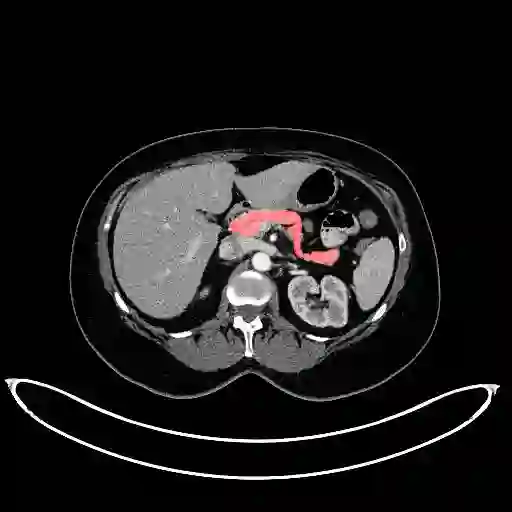

In this paper, we adopt 3D Convolutional Neural Networks to segment volumetric medical images. Although deep neural networks have been proven to be very effective on many 2D vision tasks, it is still challenging to apply them to 3D tasks due to the limited amount of annotated 3D data and limited computational resources. We propose a novel 3D-based coarse-to-fine framework to effectively and efficiently tackle these challenges. The proposed 3D-based framework outperforms the 2D counterpart to a large margin since it can leverage the rich spatial infor- mation along all three axes. We conduct experiments on two datasets which include healthy and pathological pancreases respectively, and achieve the current state-of-the-art in terms of Dice-S{\o}rensen Coefficient (DSC). On the NIH pancreas segmentation dataset, we outperform the previous best by an average of over 2%, and the worst case is improved by 7% to reach almost 70%, which indicates the reliability of our framework in clinical applications.